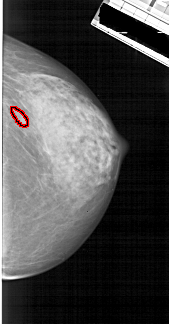

A_1912_1.RIGHT_MLO

RIGHT_MLO LINES 5491 PIXELS_PER_LINE 2581 BITS_PER_PIXEL 12 RESOLUTION 43.5 OVERLAY

FILE: A_1912_1.RIGHT_MLO.OVERLAY

TOTAL_ABNORMALITIES 1

ABNORMALITY 1

LESION_TYPE MASS SHAPE OVAL MARGINS OBSCURED

ASSESSMENT 3

SUBTLETY 3

PATHOLOGY BENIGN

TOTAL_OUTLINES 1

BOUNDARY